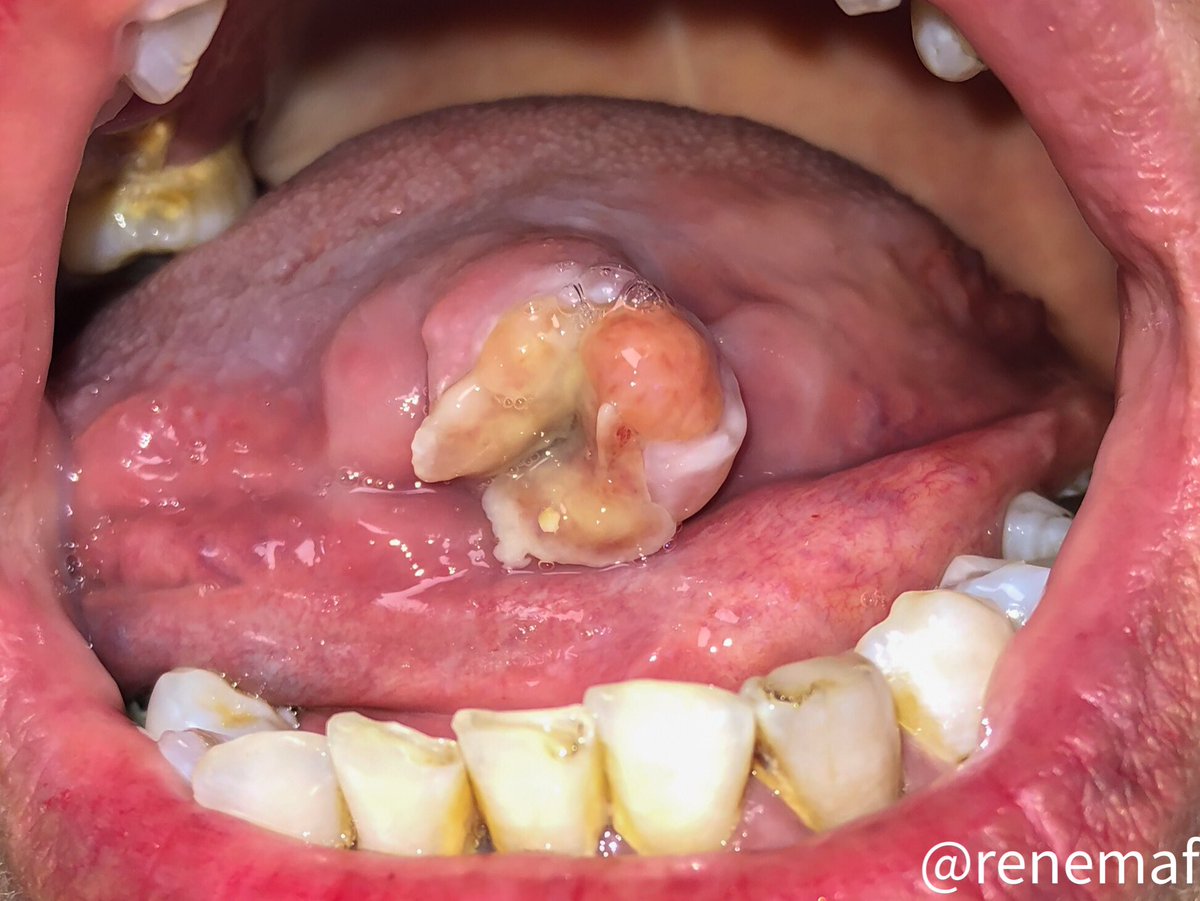

A 3 months in duration painful ulcer in a 58-yo female, without relevant medical history. An incisional biopsy was perfomed. What are you thinking ? Spot diagnosis? #oralpath #oralpathology🔬 #oralmed #oralmedicine 👀